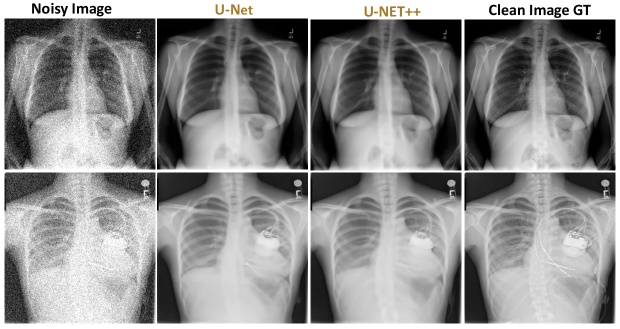

To qualitatively assess image reconstruction fidelity, we compare denoising outputs at 10%, 20%, and 30% Gaussian noise levels using representative test samples. Each comparison (Done under 1-GPU configurations) includes the noisy input, U-Net output, U-Net++ output, and the clean ground truth.

Figures 56, and 7 illustrate results at 10%, 20%, and 30% noise levels, respectively.

At 30% noise (Figure 7), U-Net visibly struggles. Texture smearing and structural loss become prominent, with ambiguous regions such as the vertebral shadow and costophrenic angle. U-Net++ remains relatively robust, with only modest blurring and clear preservation of chest wall and lung structures. Despite strong noise perturbation, U-Net++ maintains perceptual realism and continuity in critical anatomical areas.

Figure 7: Visual comparison of noisy input, U-Net and U-Net++ denoised outputs, and ground truth (30% noise levels).